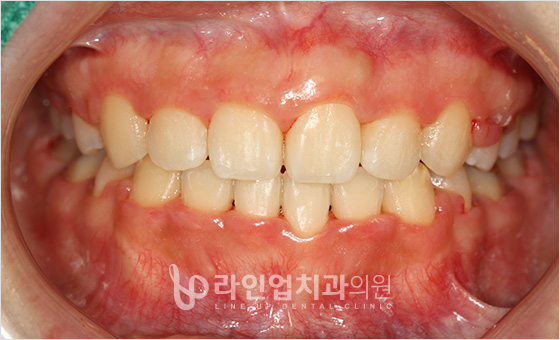

전후사진

치료전 Before

치료후 After